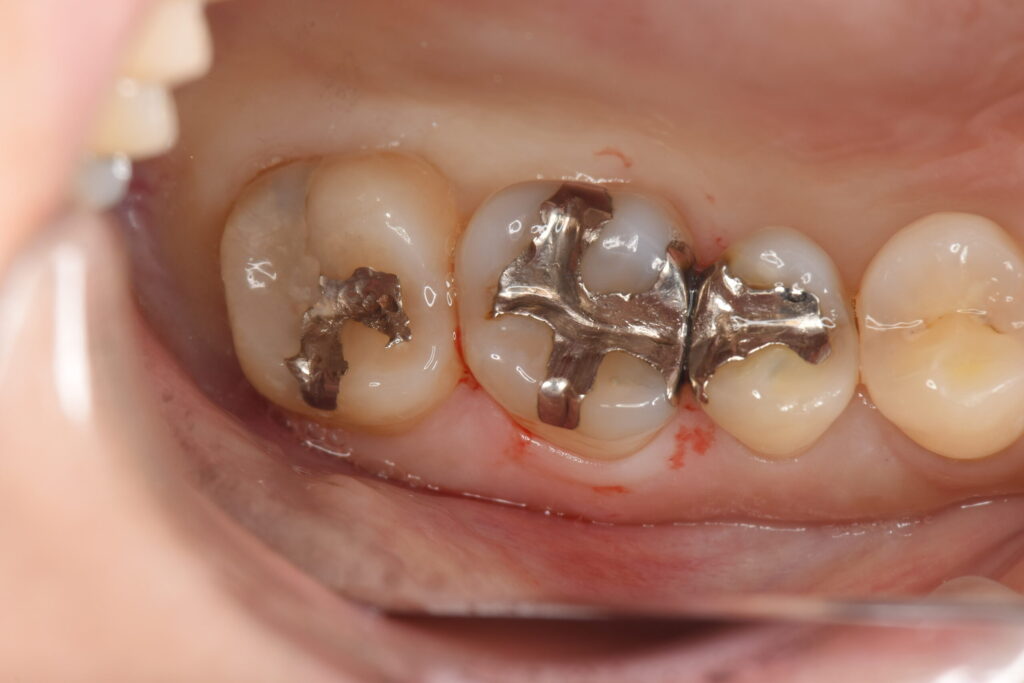

検診と気になる部位のチェックを希望されて来院された30代女性です。

レントゲン検査にて、銀歯の下に隠れた虫歯が見つかったため、治療の必要性とその選択肢、それぞれの選択肢を選んだ際の未来の予想をメリットデメリットを加えて説明。

目で見ただけでは、銀歯の下に虫歯があることはわかりません。そのような場合は、レントゲン検査でしか虫歯を見つけることができないため、すずき歯科・矯正歯科では年1回のレントゲン写真を必ず撮るようにして虫歯の発見率を上げております。